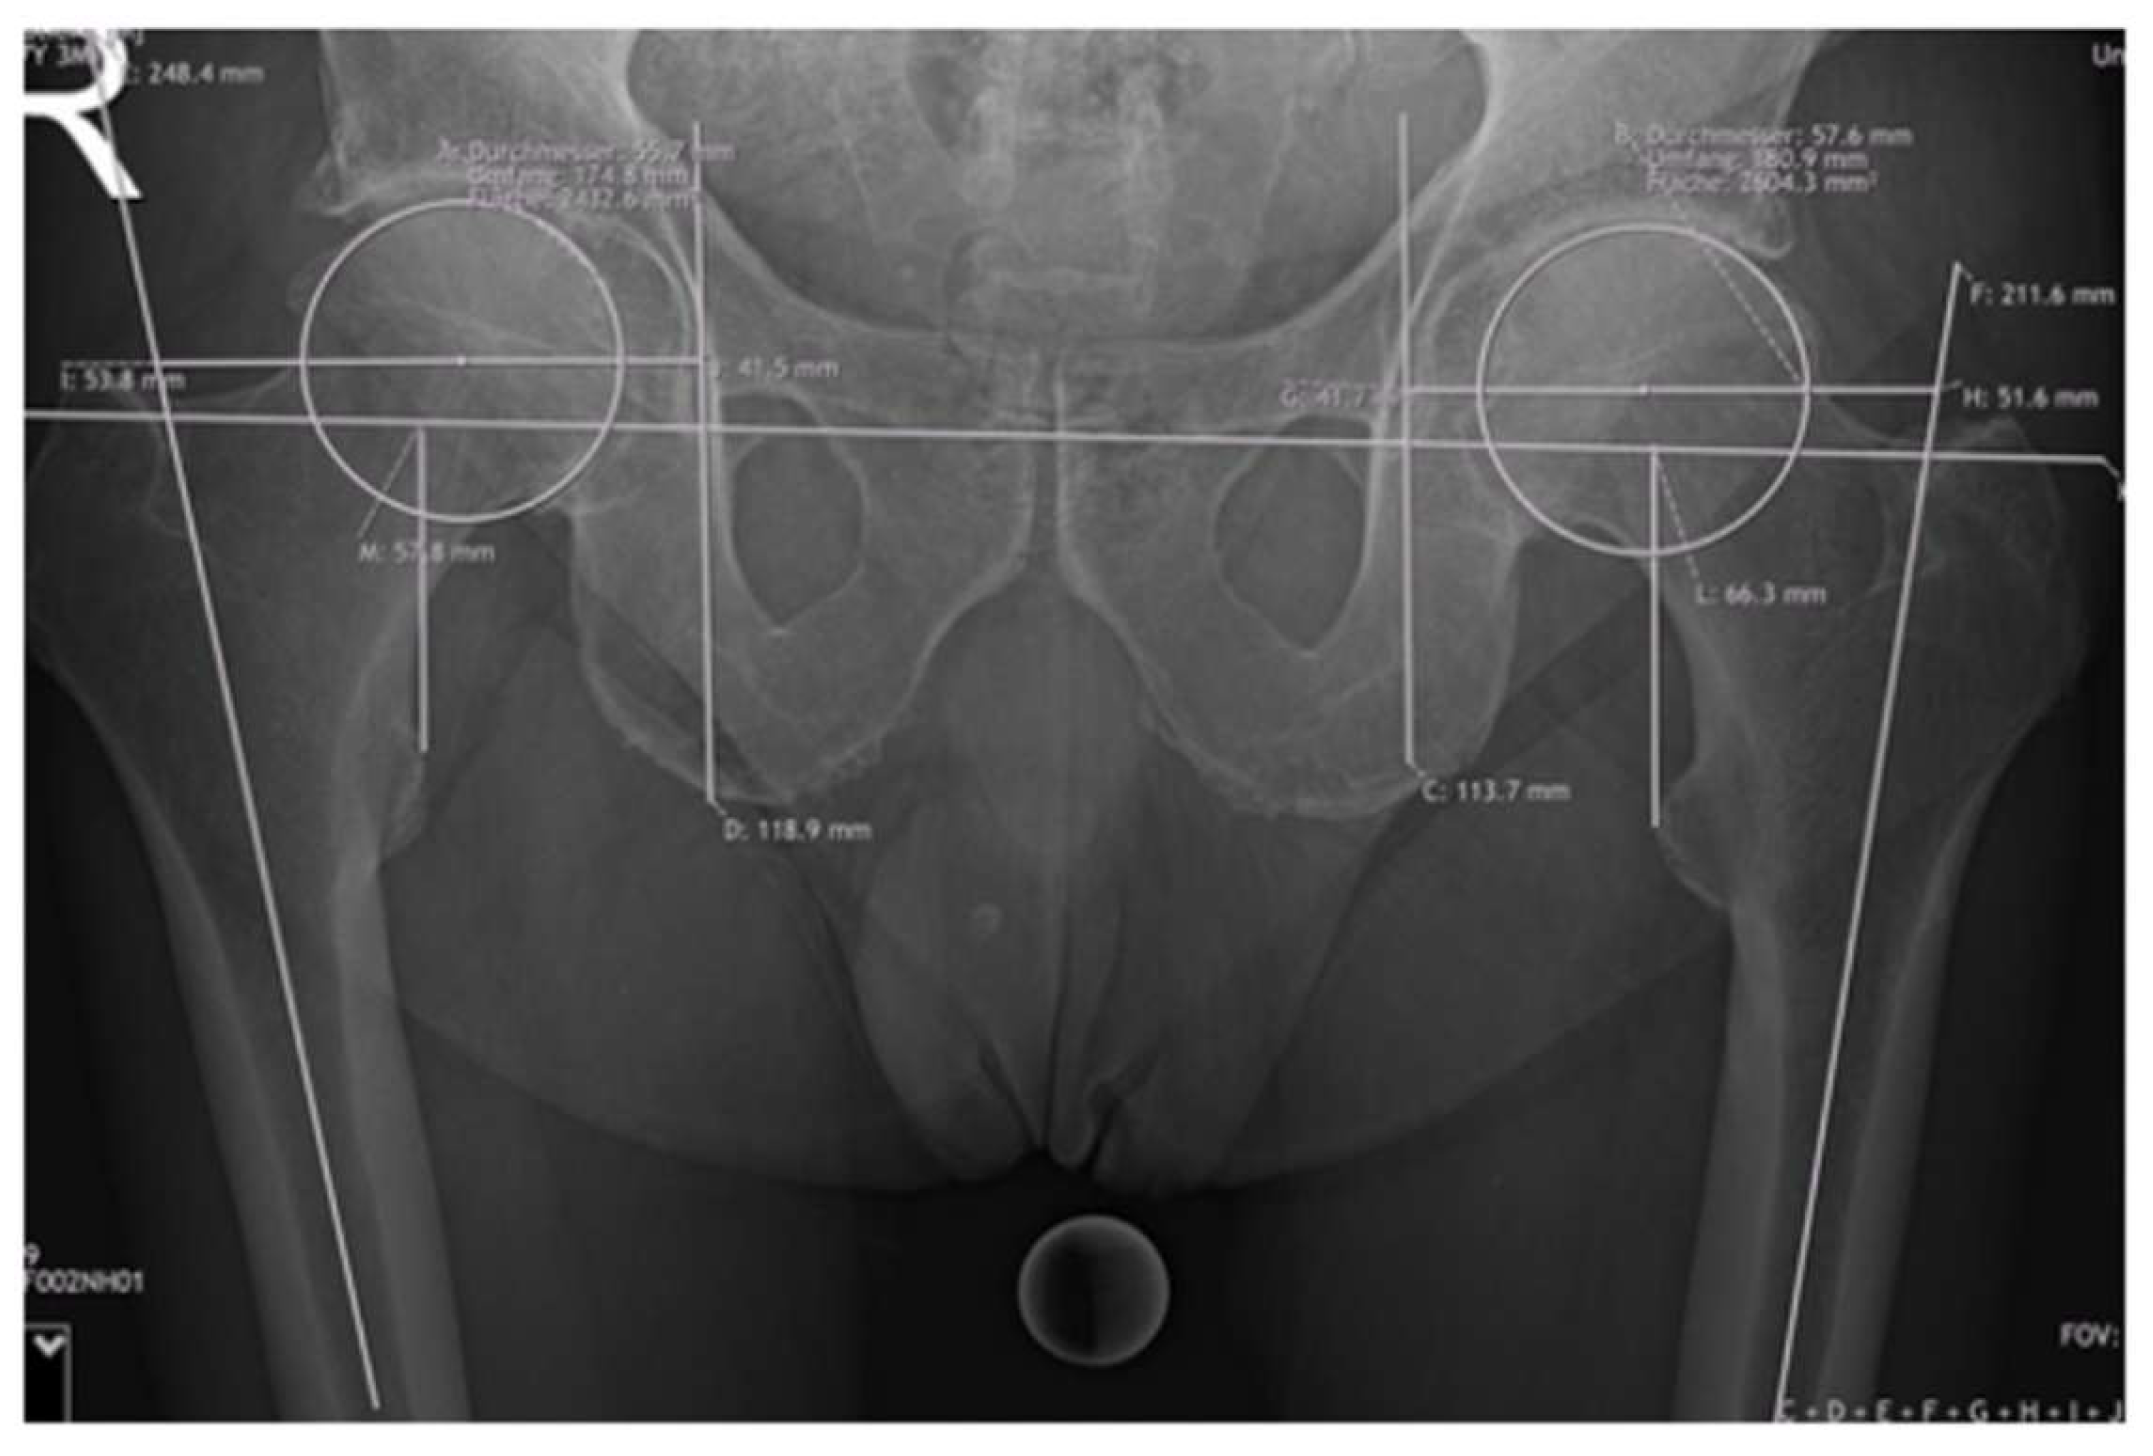

Offset measurements included femoral offset (FO) and acetabular offset (AO), resulting in the hip offset (HO). The FO was calculated as the perpendicular distance between the center of the femoral head and the axis of the femoral shaft. To measure acetabular offset, a vertical line was drawn through the teardrop, perpendicular to the interteardrop reference line. The perpendicular distance from this vertical line to the center of the femoral head was then measured and resulted in the AO. The LLD was assessed using the interteardrop line as the horizontal reference. The discrepancy was determined by calculating the difference between the vertical distances from this reference line to the most prominent points on each lesser trochanter. Detailed information about the measurements are shown in Figure 3.

Figure 3. Measurements of FO, AO, HO, and leg length on a preoperative radiograph.